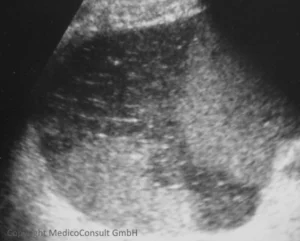

Normale Milz